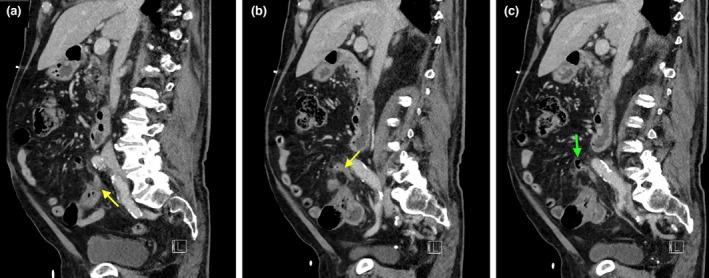

Complicated appendicular diverticulitis.

Appendiceal diverticulitis, a frequently underdiagnosed entity, differs from typical appendicitis by the presence of an inflamed appendiceal diverticulum. Appendiceal diverticulitis is a surgical emergency which has an increased risk of perforation compared to typical appendicitis. We will discuss a surgically and pathologically confirmed case of complicated appendiceal diverticulitis and its management implications.